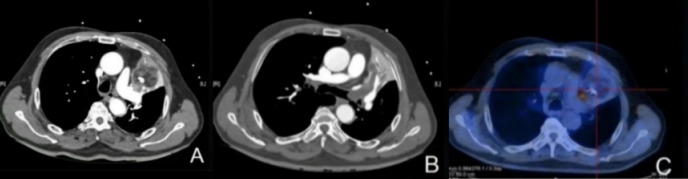

原发性肺脂肪肉瘤极为罕见。迄今为止,在英国文献中仅报道了24例。在此,我们报告一例高分化肺脂肪肉瘤,在正电子发射断层扫描/计算机断层扫描(CT)和增强CT上被误诊为畸胎瘤。行根治性手术,左上肺叶切除及纵隔淋巴结清扫。患者术后33个月出现复发和远处转移。在撰写本报告时,患者还活着(术后36个月)。据我们所知,这是第一例肺高分化脂肪肉瘤的报告。

Primary liposarcoma of the lung is extremely rare. To date, only 24 cases have been reported in the English literature. Herein, we present a case of well-differentiated pulmonary liposarcoma that was misdiagnosed as teratoma on positron emission tomography/computed tomography (CT) and contrast-enhanced CT. Radical surgery with left superior lobectomy and mediastinal lymph node dissection were performed. The patient experienced recurrence and distant metastases 33 months after surgery. He was alive at the time of writing this report (36 months postoperatively). To our knowledge, this is the first case report of pulmonary well-differentiated liposarcoma.